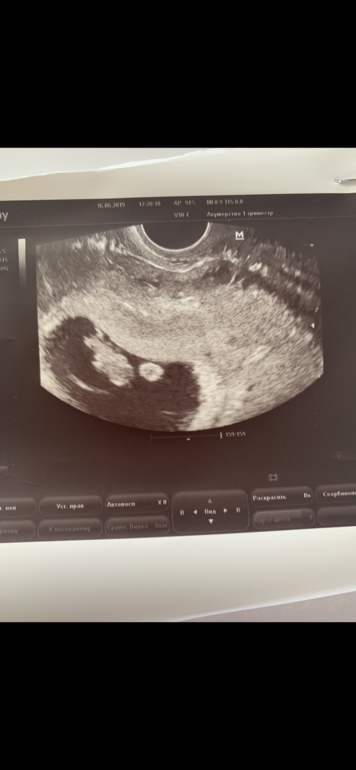

девочки,подскажите может кто у нас будет)врач ничего не говорила)срок 12.5

Здравствуйте. Как думаете мальчик или девочка? фото 9 недель., 13 почт

И 13 недель то есть. В первый раз сказали мальчик

Во второй девочка))